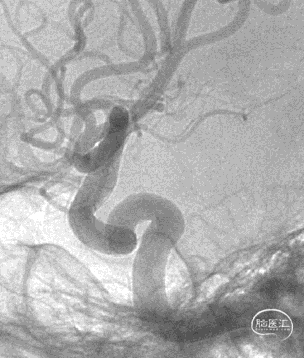

术后半年复查

7、术后半年复查动脉瘤治愈,且未发生支架远近端狭窄及内膜过度增生,治疗效果满意。

8、同侧A1动脉瘤在FD保护下无变化。